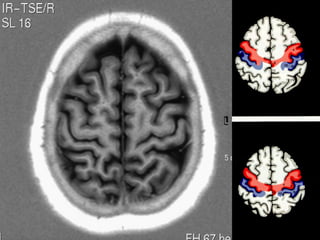

LOBO PARIETAL

Giro

Parietal

Superior

Angular

Supra marginal

• 2 sulcos / 3 giros .

• Sulcos pós central( paralelo cissura de Rolando )

e intra parietal .

• Giros parietal superior e inferior ( separados pelo

sulco intra parietal )

giro parietal ascendente ( pós central )     principal

área somato sensitiva cortical